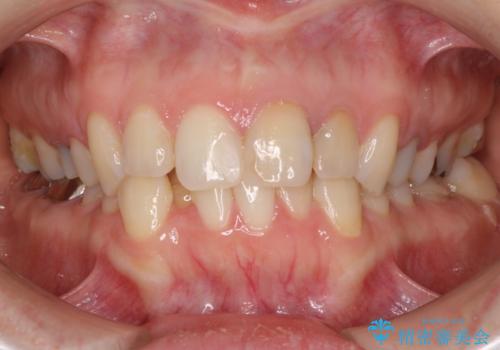

【モニター】前歯のデコボコと奥歯の虫歯 インビザライン治療と奥歯のセラミック治療

- 前歯のデコボコと奥歯の虫歯を気にして来院された患者様です。

主に下顎歯列全体の後方移動とIPR(歯と歯の間を削る)によってデコボコが解消するように設計し、インビザラインにより治療を行うこととしました。

矯正治療後半に下顎左右奥歯をセラミッククラウンにて補綴し、その後インビザラインによる歯列の仕上げを行うこととしました。

下顎前歯の叢生が速やかに改善されたため、1年3か月で治療を終えることができました。

下顎前歯は後戻りを起こしやすいため、舌側を細いワイヤーで固定することで後戻り対策を行っています。